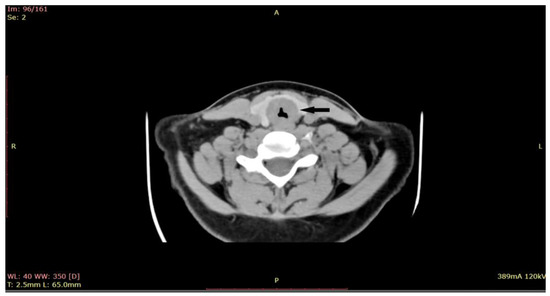

Given the critical nature of the patient’s condition, an immediate intervention was performed before sending the patient for a CT scan. Emergency tracheostomy was performed to secure the airway. However, during the operation, the patient developed a spontaneous left pneumothorax, which necessitated pleural drainage. The aim of the procedure was to secure the airway, relieve respiratory distress, and obtain a biopsy for further diagnosis. Once the patient’s condition stabilized after the pleural drainage, a biopsy of the subglottic tumor was obtained through direct laryngoscopy. During the direct laryngoscopy procedure, a tumor formation was observed in the subglottic region, involving the first tracheal ring. On examination, the tumor appeared slightly indurated, with smooth local mucosa. It circumferentially covered the subglottic area with marked narrowing of the respiratory space. A computed tomography (CT) scan was performed (Figure 2), which showed subglottic mass involving the trachea, with marked circumferential and slightly asymmetrical thickening of the laryngeal walls, from a plane passing through the arytenoid cartilages, involving the cervical trachea until the distal space C7-T1, with marked intraluminal stenosis (71%) and compression of the thyroid lobes.

Figure 2. CT of the larynx shows a subglottic submucosal mass with marked intraluminal stenosis (at the arrow)-axial plane.